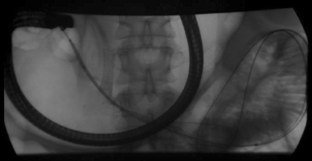

Figure 1

Figure 2

Figure 3

Figure 4

Figure 5